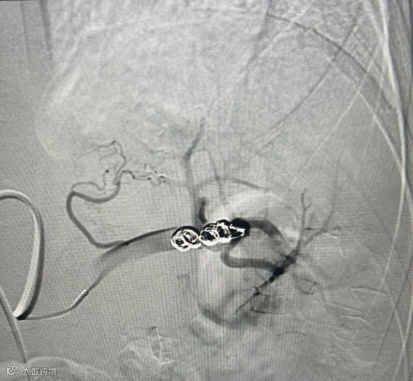

然而,血管外科介入团队沉着冷静,如同精准的导航,通过微导管超选择地将栓塞材料送至出血的血管。瞬间,造影显示活动性出血显著减少,被成功阻断!一场生命的危机,在几乎无创的条件下被化解。

造影脾动脉栓塞以远动脉显影减少,血流速度明显减慢,远端动脉分支造影剂外渗明显减少。